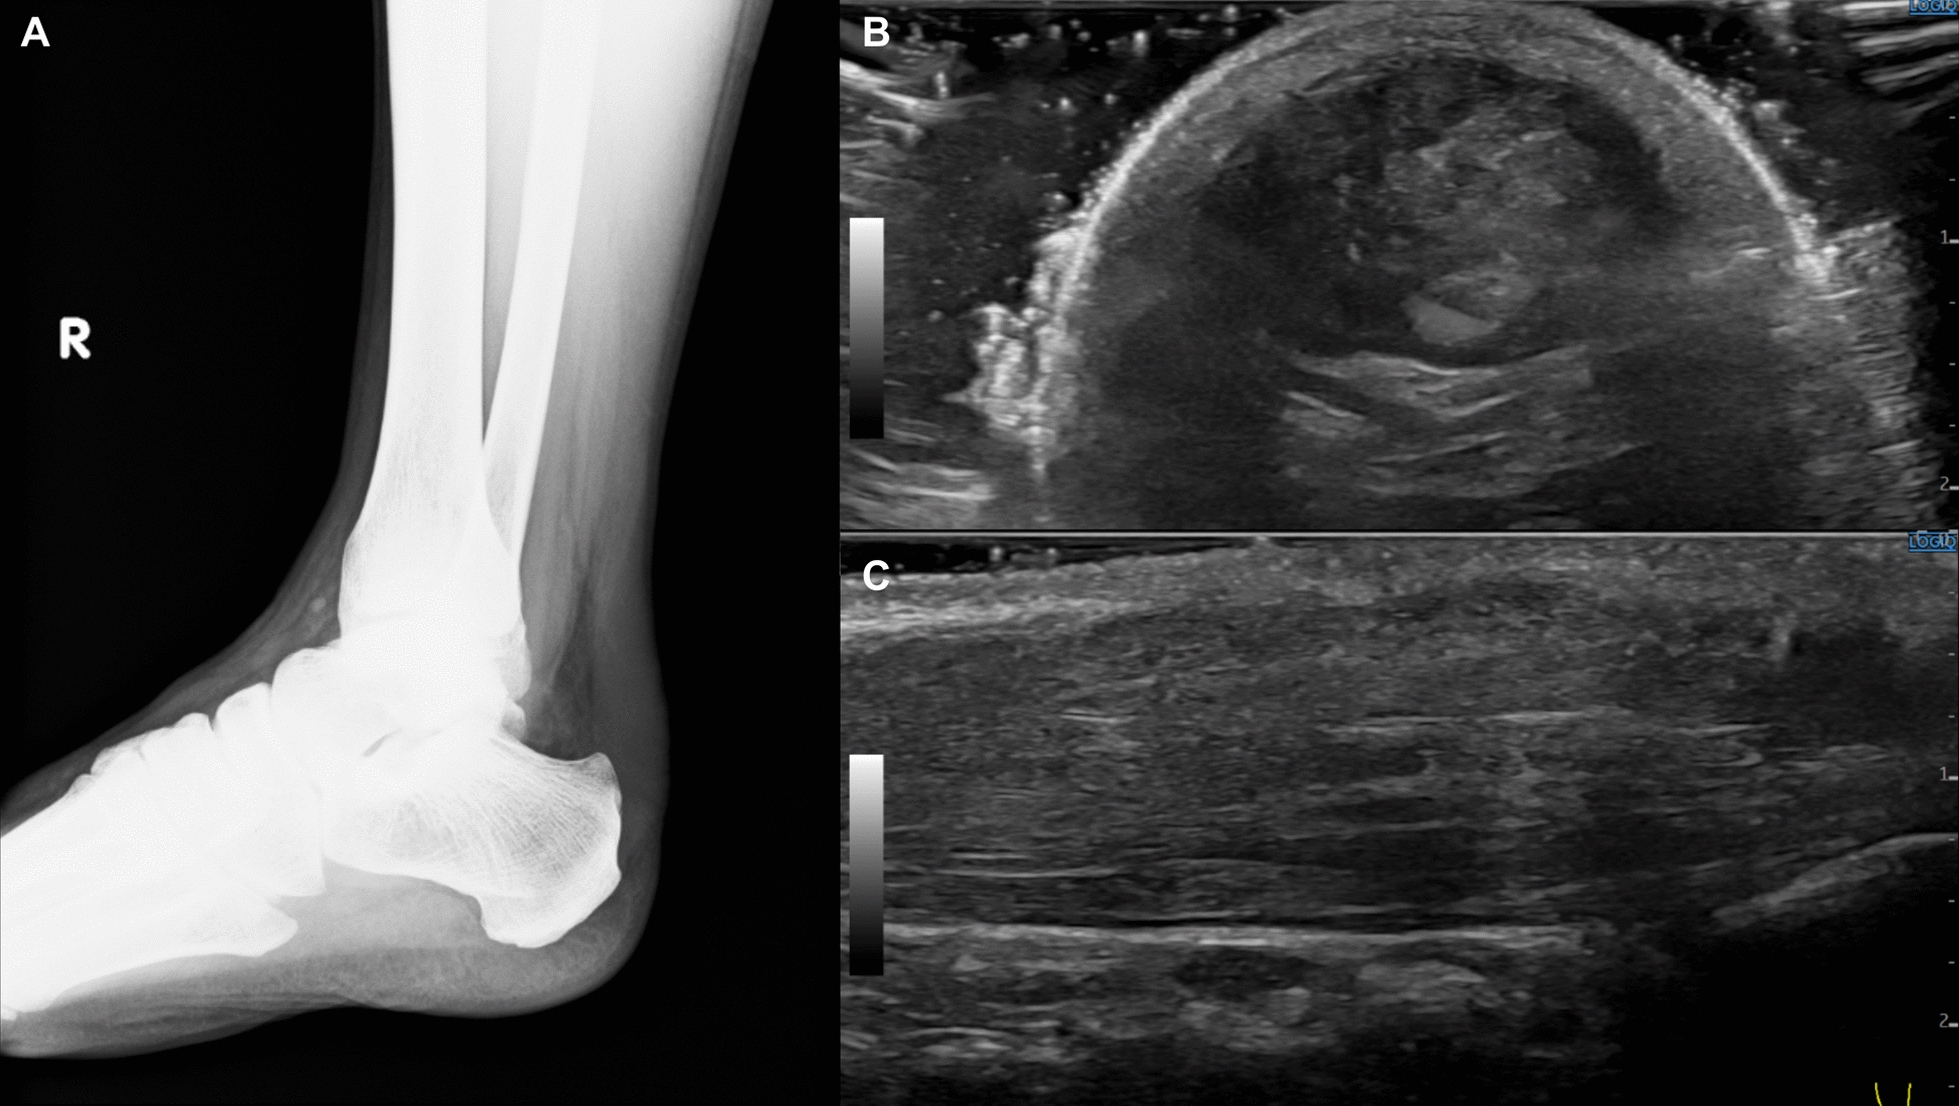

Case presentation: We report a 53-year-old Japanese man who was clinically diagnosed with familial hypercholesterolemia. He presented with marked Achilles tendon xanthomas and refractory hyper-low-density-lipoprotein cholesterolemia. Initiation of intensified lipid-lowering therapy, including inclisiran, resulted in improvement of hyper-low-density-lipoprotein cholesterolemia. Genetic testing revealed heterozygous mutations in CYP27A1 (p.Arg405Gln) and apolipoprotein B (APOB) (p.Pro955Ser). He had no neurological symptoms, cataracts, or other features suggestive of cerebrotendinous xanthomatosis without Achilles tendon xanthomas.

Conclusion: This case highlights a rare presentation of a potential CYP27A1 heterozygous mutation-related phenotype. The APOB (p.Pro955Ser) variant is associated with reduced low-density-lipoprotein receptor activity, contributing to hyper-low-density-lipoprotein cholesterolemia and Achilles tendon xanthomas. However, this patient's Achilles tendon xanthoma was thicker than those reported in previous cases with APOB (p.Pro955Ser) gene mutations, suggesting a potential contribution from the CYP27A1 mutation. Although the patient did not exhibit elevated serum cholestanol levels or other cerebrotendinous xanthomatosis features, the marked Achilles tendon thickening raises the possibility that the combination of a heterozygous CYP27A1 gene mutation and an APOB gene mutation contributed to the condition.